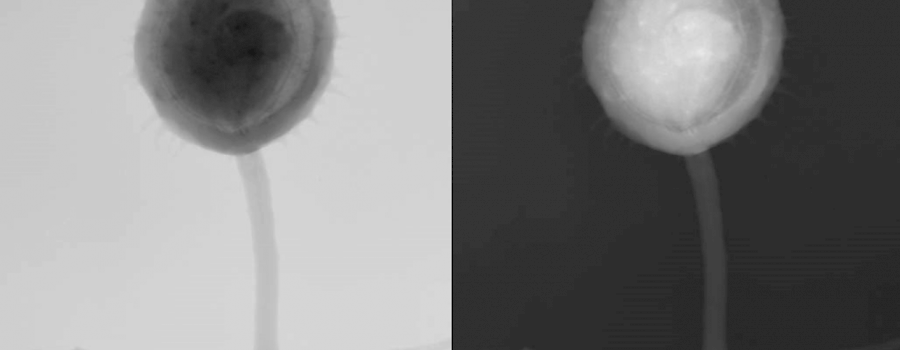

Der kleine Röntgen-Ratespaß (29)

Was ist auf unserem heutigen ominösen Röntgenbild abgebildet?